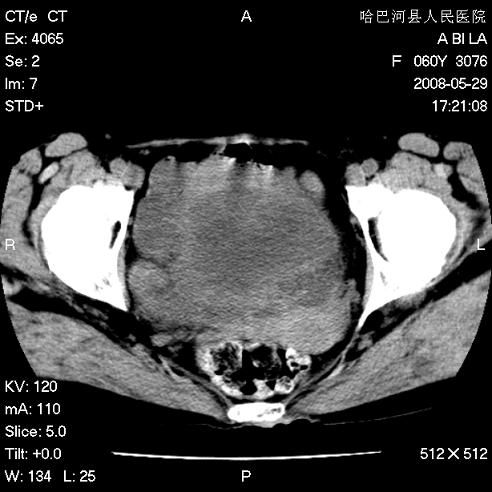

标题: CT13730:排尿不畅4天,抗炎治疗无效,现尿中可见血块 [打印本页]

标题: CT13730:排尿不畅4天,抗炎治疗无效,现尿中可见血块

膀胱癌伴转移。

膀胱癌伴转移。 支持。

膀胱内多发恶性占位,癌可能性大

手术结果及病理:膀胱癌并膀胱壁转移,膀胱内血块